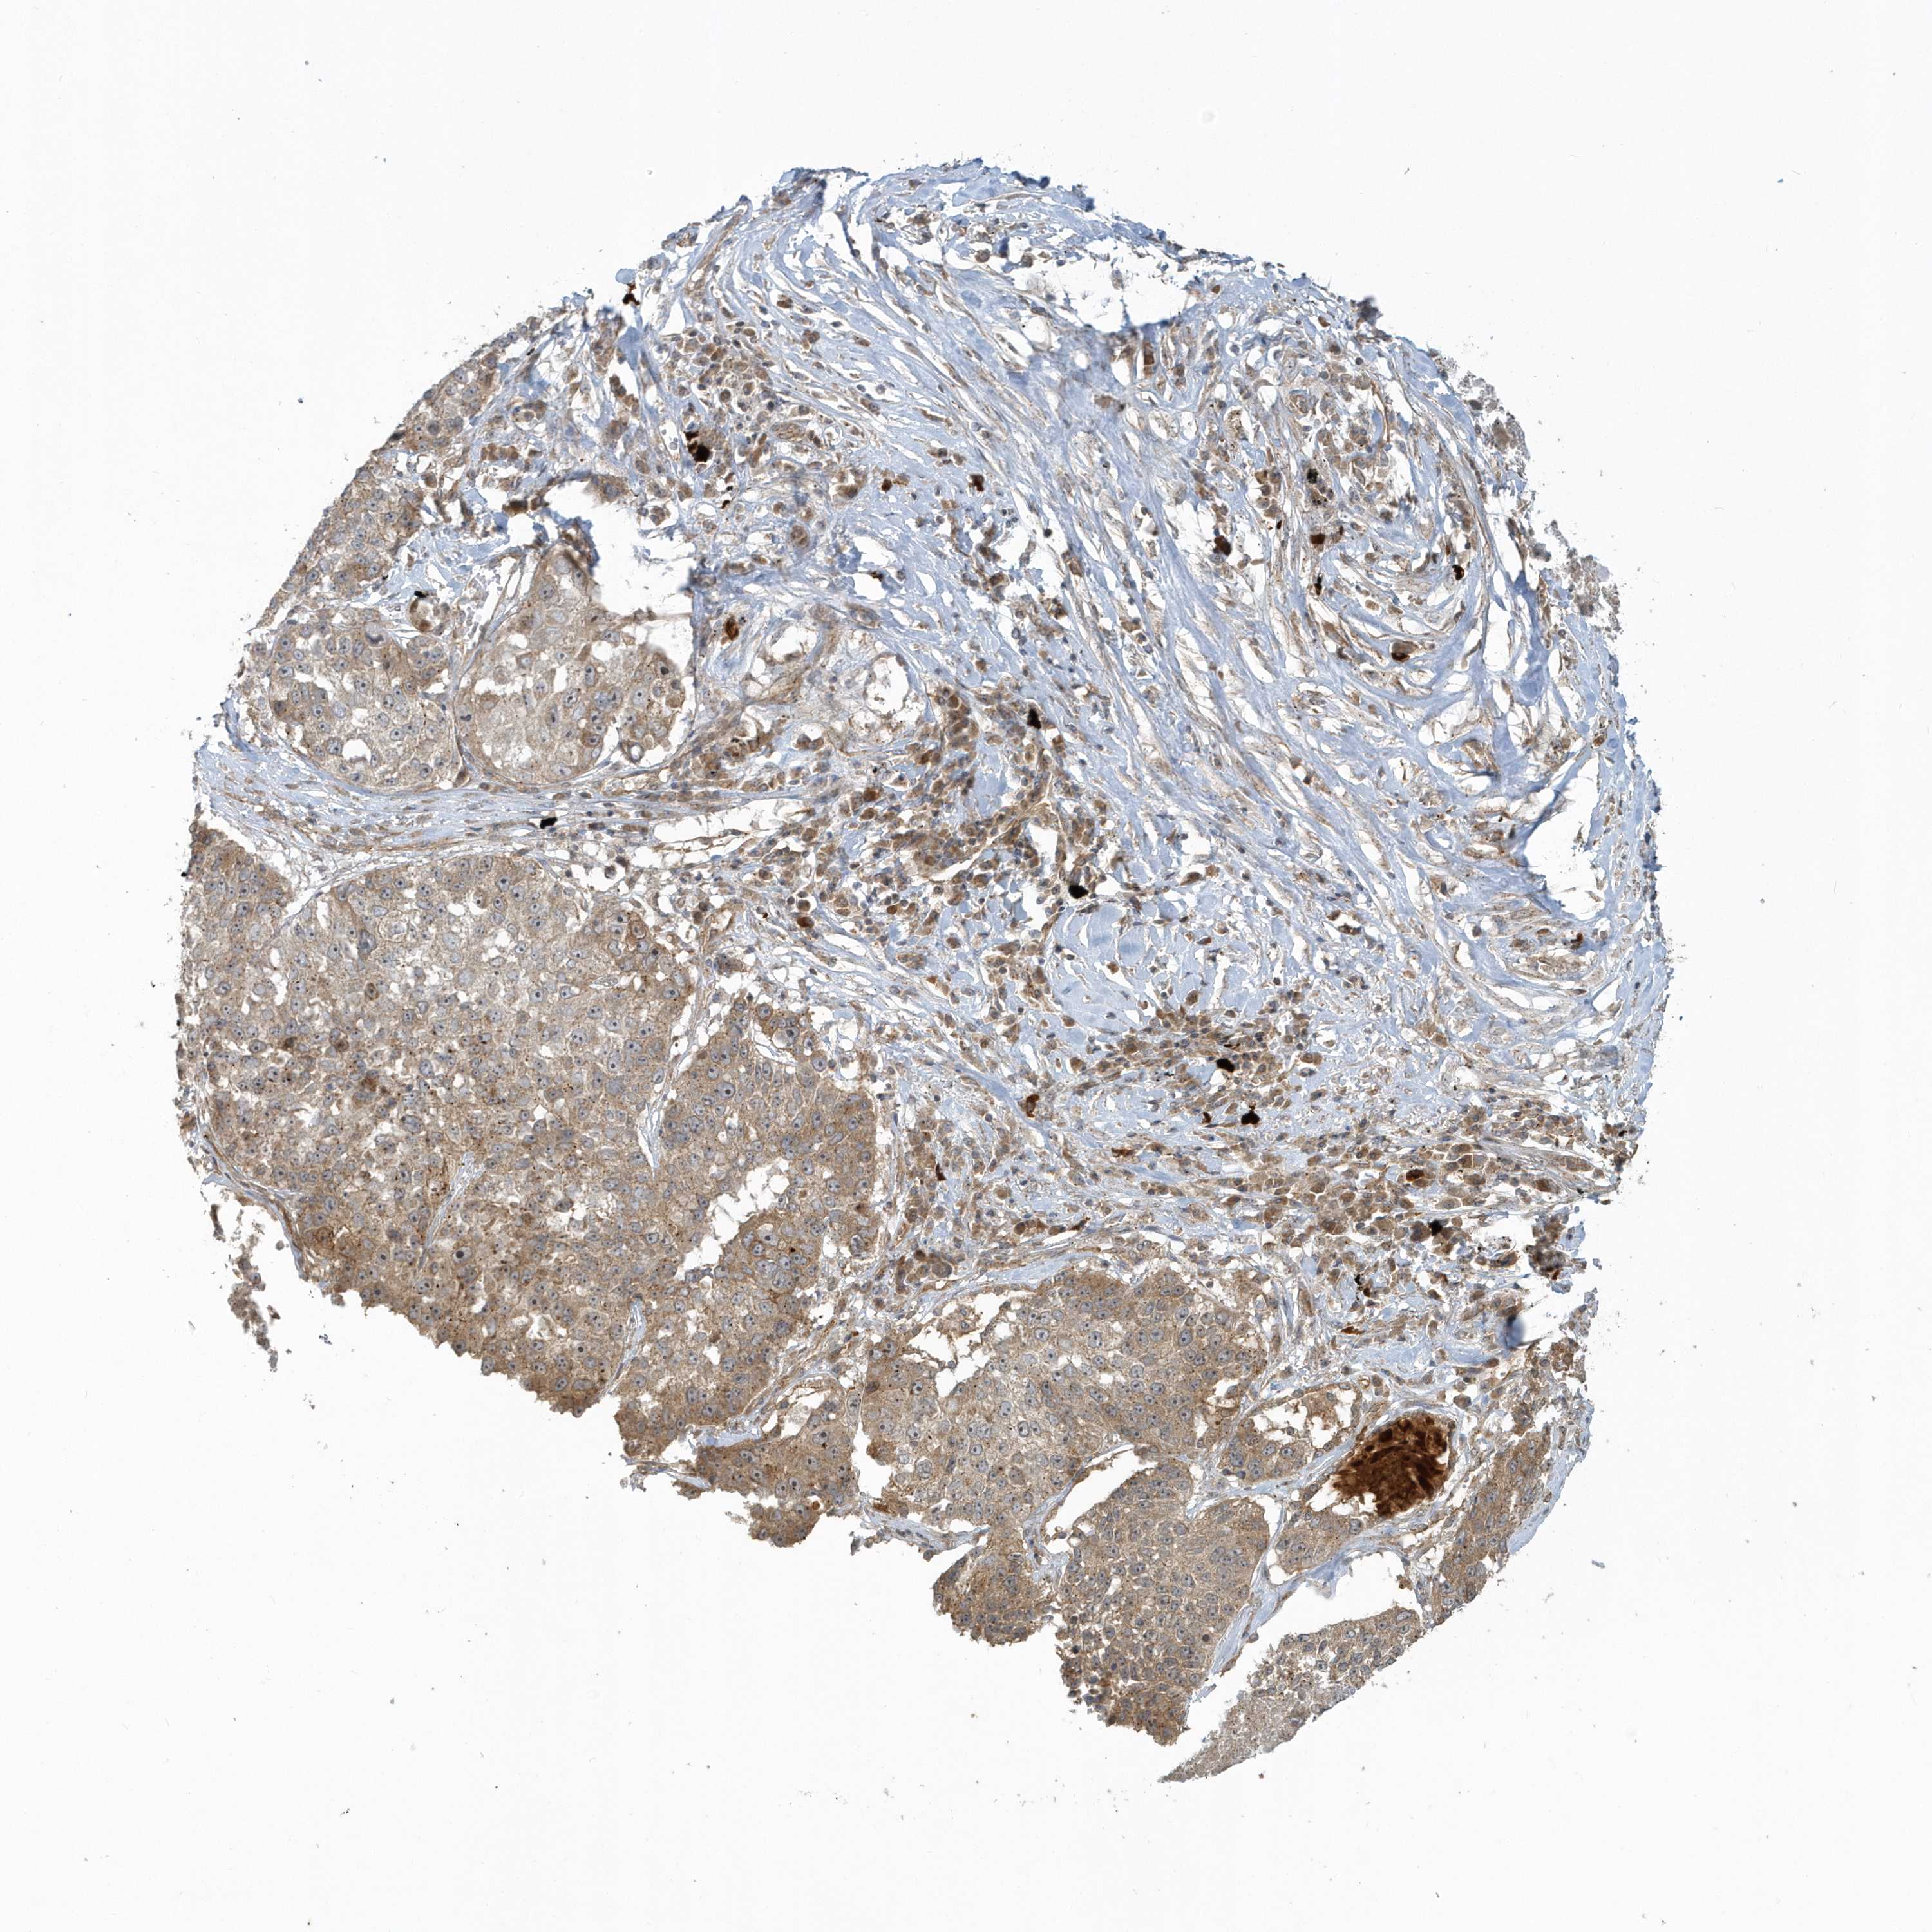

CANCER LUNG CANCER Show tissue menu

LUAD TCGA LUAD VALIDATION LUSC TCGA LUSC VALIDATION PROTEIN LUAD CPTAC PROTEIN LUSC CPTAC PROTEIN EXPRESSION